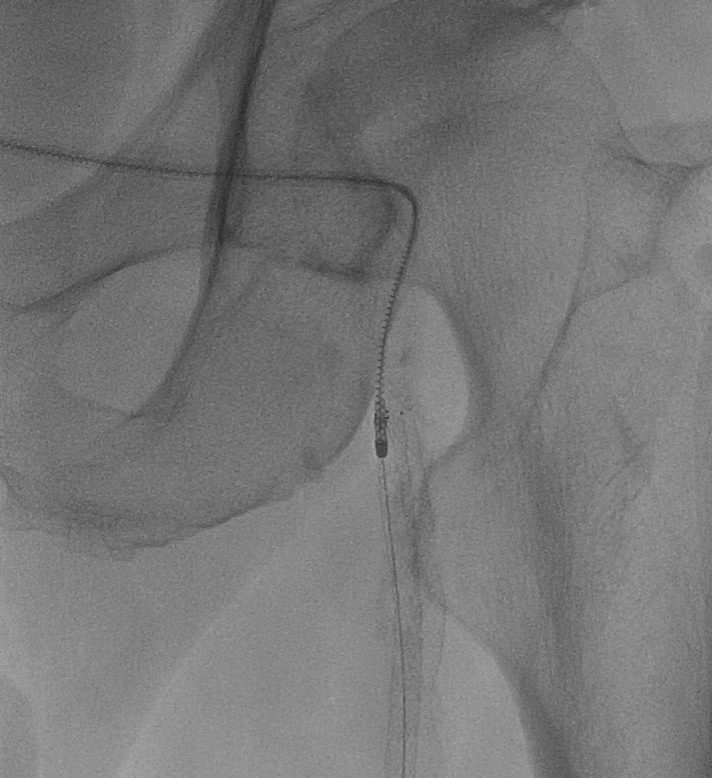

(图7)股总动脉分叉区造影

首先尝试顺行通过股浅动脉病变,依次使用V-18导丝、Connect Flex导丝、Astato 30导丝均无法顺利进入股浅动脉真腔,遂选择逆向穿刺膝下腘动脉(图8),利用Astato 30配合Seeker-18支持导管逆向通过股浅动脉闭塞段,顺利自6F鞘中引出,Saber 4*150mm球囊预扩张(图9)。

(图8)顺行通过病变失败,选择经腘动脉逆穿

接着再次尝试顺行通过股深动脉病变,然而导丝始终无法顺利找到股深动脉开口,遂再次逆穿远端股深动脉,利用Command18导丝逆向通过股深动脉病变,自6F鞘中引出,自此,股动脉分叉病变顺利完成双导丝置入(图10)。

(图10)顺行开通股深动脉失败,逆穿远端股深动脉